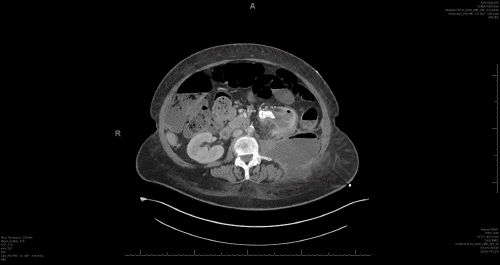

A 62-year-old female who smokes tobacco, with a history of asthma and pyelonephritis, failed outpatient empiric antibiotic treatment and was admitted for sepsis secondary to pyelonephritis with staghorn calculi, severe left hydronephrosis, and a left-sided retroperitoneal abscess (Figure 1).

Figure 1. CT Images at Admission. Published with Permission

A) Coronal view showing loculated fluid collection/abscess containing air bubbles and air-fluid level in the left retroperitoneum, measuring 10.0 × 9.5 × 9.8 cm, extending along the left psoas muscle and beyond the abdominal musculature into the soft tissues of the left flank

B) Large 3.3 cm staghorn calculus in the left kidney, resulting in severe left hydronephrosis and likely calyceal rupture

C) Coronal view on the left showing the connection between the descending colon and left kidney (arrow) and the same pathology shown on the axial view on the left indicated by crossmarker.

D) Status postpercutaneous left nephrostomy (red arrow) and catheter drainage of the left retroperitoneal abscess (blue arrow)